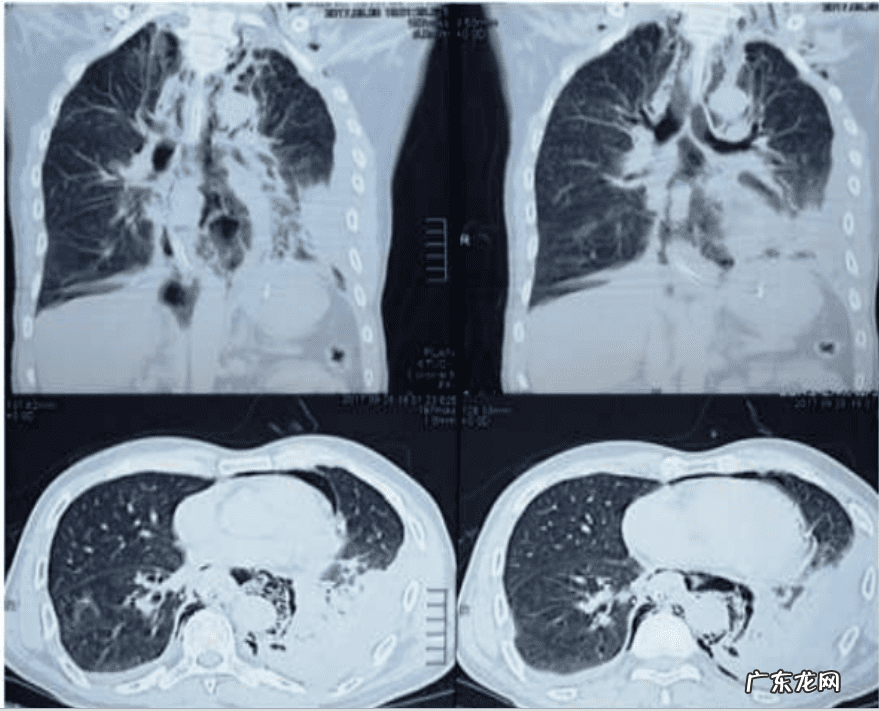

入院30分钟后,患者外周血氧开始下降,查体发现胸壁和颈部有皮下气肿 。胸部CT发现纵隔气肿以及颈部和左外侧胸部皮下气肿(图3),上消化道内窥镜检查显示出食管穿孔(图4) 。该患者经内镜支架置入治疗,后在重症监护病房在无创通气支持治疗2天,患者最终恢复良好,康复出院 。

图3 急诊胸部CT影像